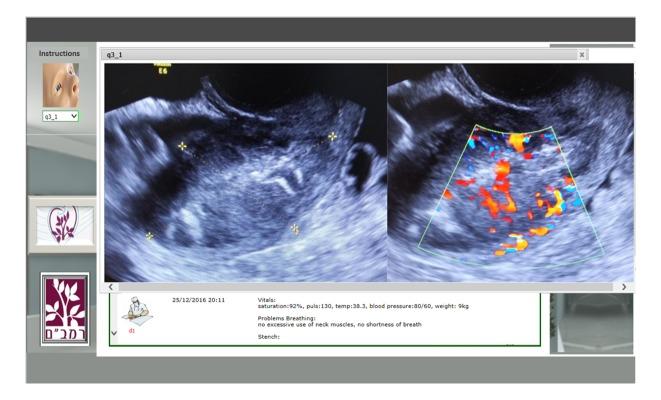

This quantitative study assessed the effectiveness of a computerized interactive simulator coupled with an instructor who monitored students' progress and provided Web-based immediate feedback.

A low-cost, globally accessible, telemedicine simulator, developed at the Technion-Israel Institute of Technology, Haifa, Israel-was used. A previous study in the field of interventional cardiology, evaluating the efficacy of the simulator to enhanced learning via knowledge exams, presented promising results of average scores varying from 94% after training and 54% before training (n=20) with P<.001. Two independent experiments involving obstetrics and gynecology (Ob-Gyn) physicians and senior ultrasound sonographers, with 32 subjects, were conducted using a new interactive concept of the WOZ (Wizard of OZ) simulator platform. The contribution of an instructor to learning outcomes was evaluated by comparing students' knowledge before and after each interactive instructor-led session as well as after fully automated e-learning in the field of Ob-Gyn. Results from objective knowledge tests were analyzed using hypothesis testing and model fitting.